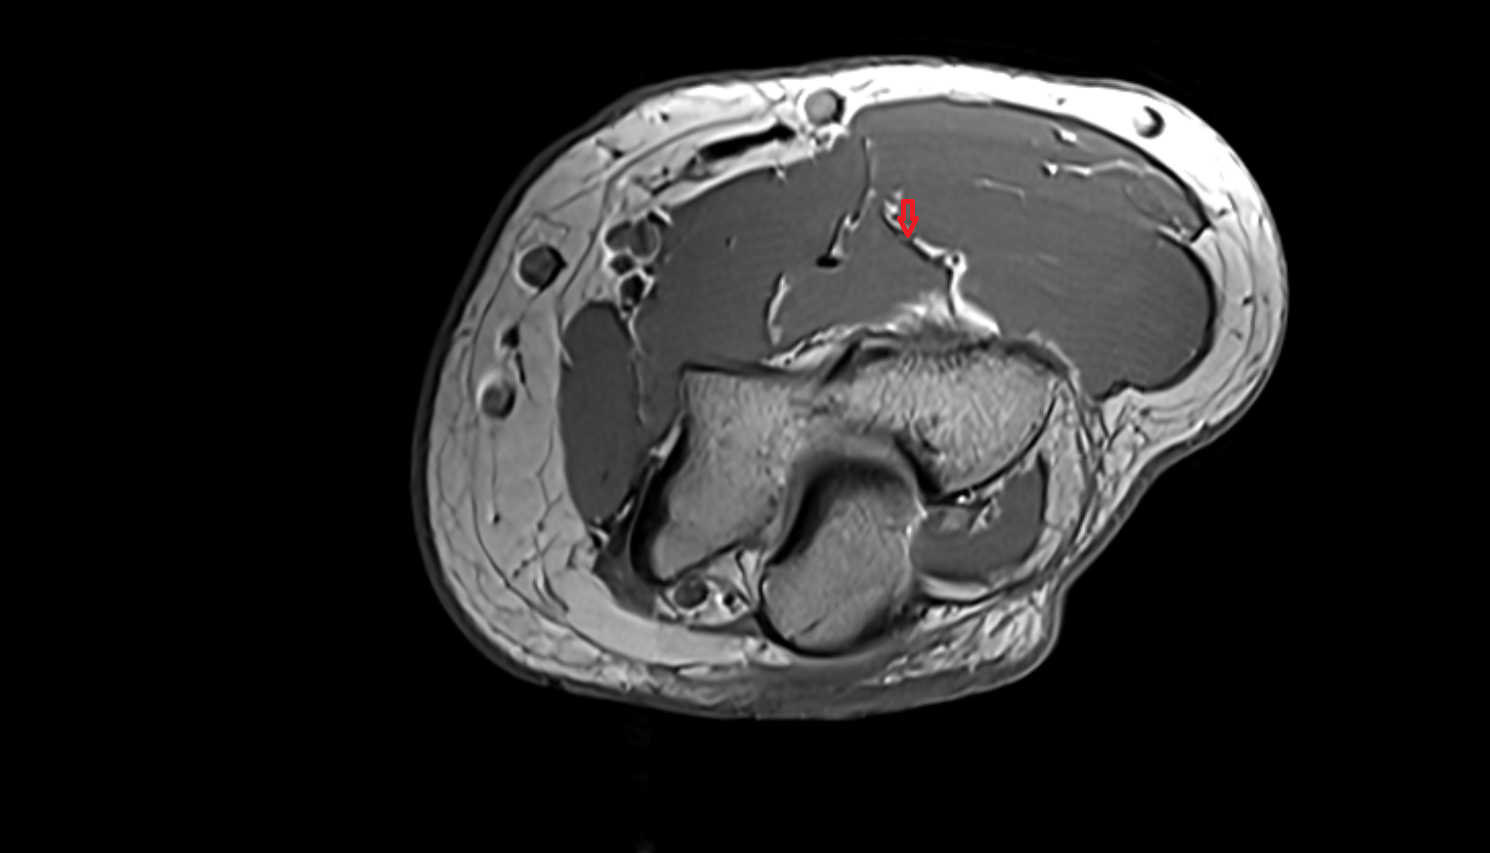

- Knee Joint